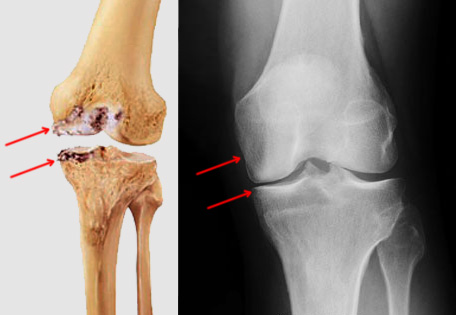

In determining whether a knee replacement is right for you, an orthopedic surgeon assesses your knee's range of motion, stability and strength. X-rays help determine the extent of damage.

A total knee replacement is a surgical procedure whereby the diseased knee joint is replaced with artificial material. The knee is a hinge joint that provides motion at the point where the thigh meets the lower leg. The thighbone (or femur) abuts the large bone of the lower leg (tibia) at the knee joint. During a total knee replacement, the end of the femur bone is removed and replaced with a metal shell. The end of the lower leg bone (tibia) is also removed and replaced with a channelled plastic piece with a metal stem. Depending on the condition of the kneecap portion of the knee joint, a plastic "button" may also be added under the kneecap surface. The artificial components of a total knee replacement are referred to as the prosthesis.